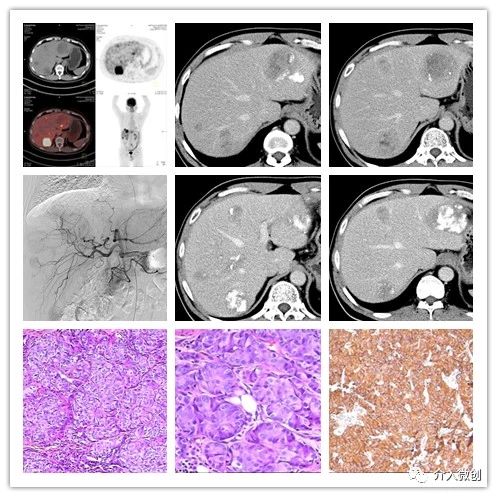

例3:肺神经内分泌瘤(G1)术后肝、骨多发转移

- 中年男性,左下肺类癌(G1)切除术后6年余。

- PET-CT显示肝内见多个结节状及块状低密度占位性病变,大部分病灶代谢增高,部分病灶代谢未见增高,考虑为肝脏内多发转移灶。

- 肝脏转移瘤行多次介入栓塞治疗,控制良好。

肺神经内分泌瘤(G1)